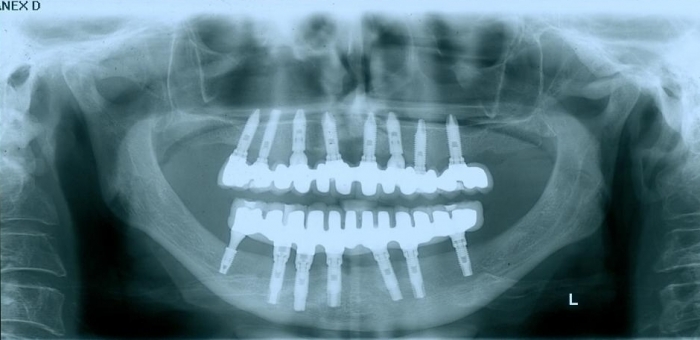

Imagem implantes Superiores em 2009 - Clínica Cliniface

Imagem implantes Superiores em 2009